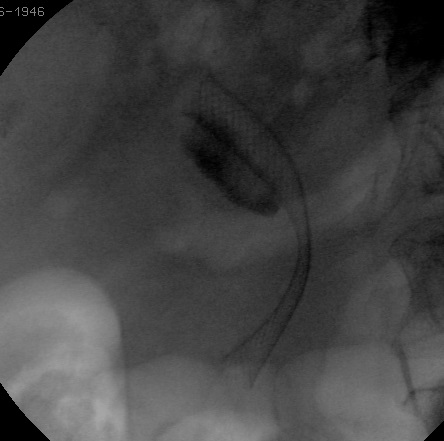

CPRE avec Prothèse biliaire pour cancer du pancréas

Le drainage biliaire palliatif, par CRE avec mise en place d’une prothèse, a supplanté la chirurgie de dérivation biliaire depuis le développement des prothèses métalliques. En effet, leur diamètre assure le maintien de leur perméabilité dans 82 et 78 % des cas à 6 et 12 mois, respectivement, alors que la survie moyenne des patients avec des cancers localement avancés ou métastatiques est de 4 à 8 mois.